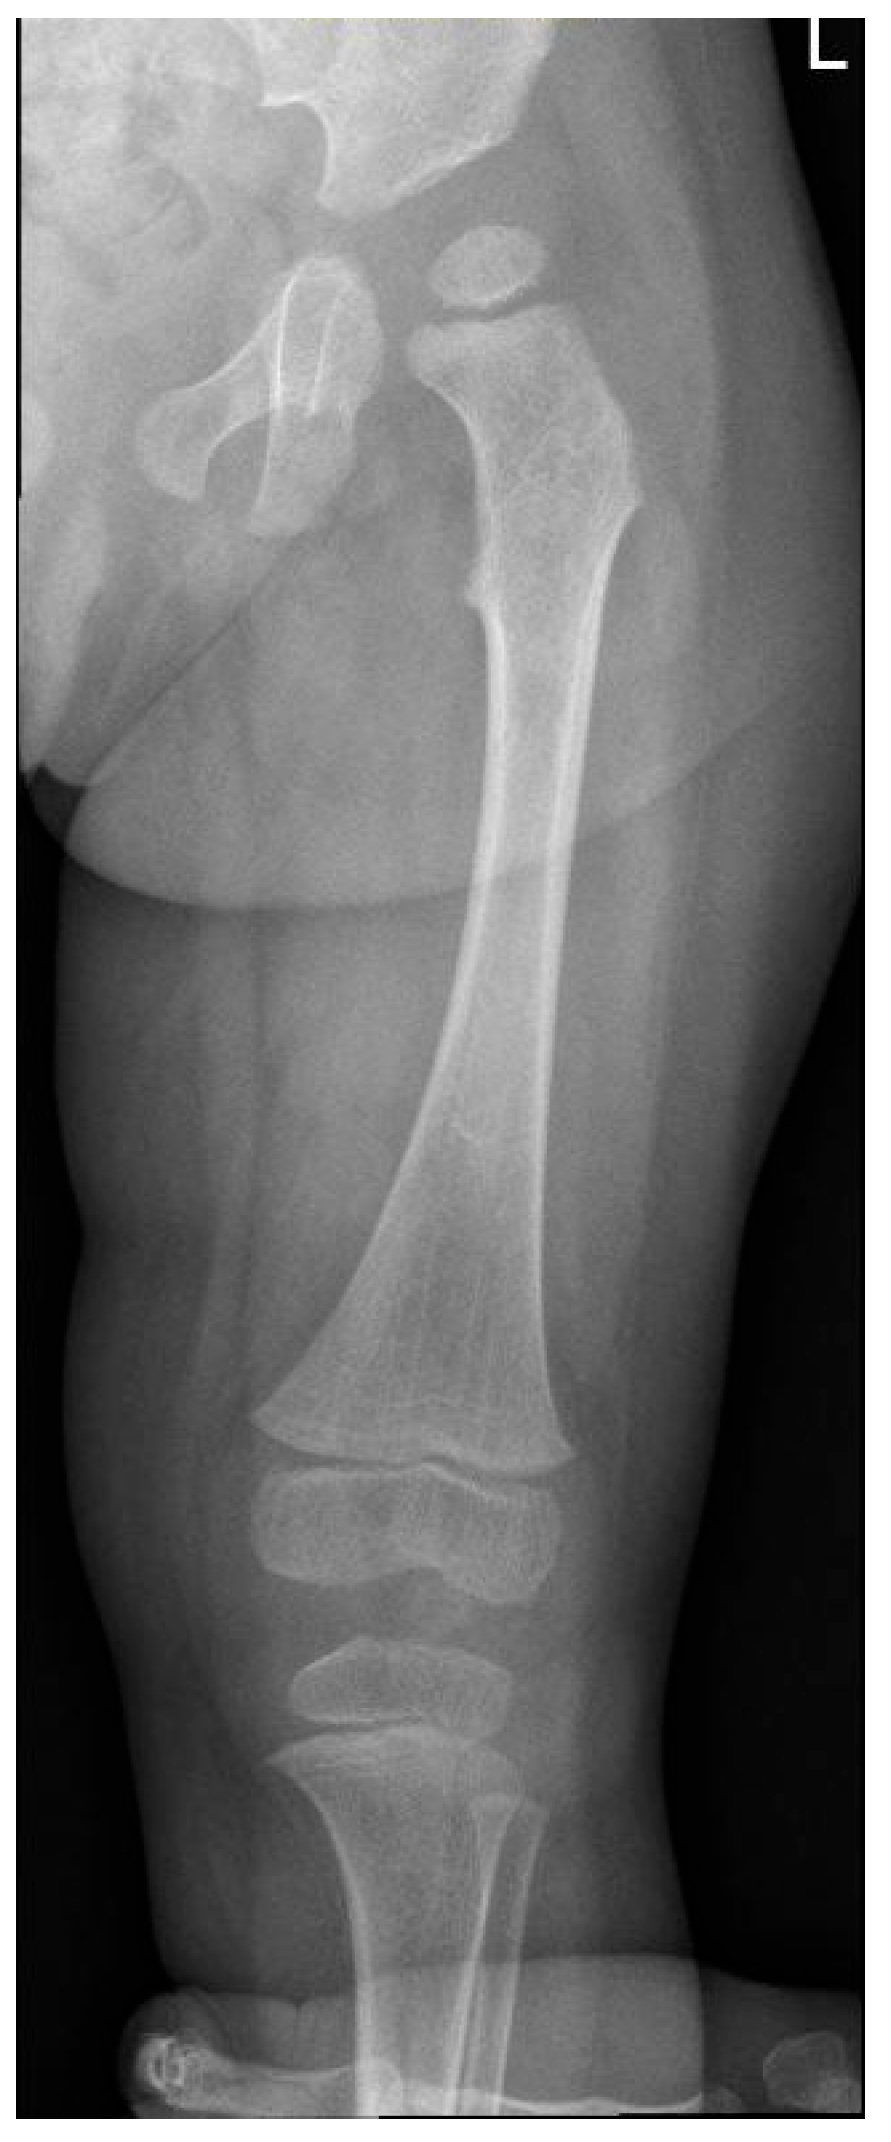

| Hip dysplasia | + | + | + | + | + | + | + | + |

| Dysmorphic long bones | + | + | + | + | + | + | ||

| P1 (MPSI) | Baseline | RX | Pelvis | Mild iliac wing hypoplasia; shifty acetabular roofs. |

| RX | Hands | Short, thickened metacarpal bones; tapered proximal ends. | ||

| After 3 years of ERT | RX | Pelvis | Thickening of the acetabular roofs. | |

| RX | Hands | Progression of the metacarpal deformities; malformative aspects of radius and ulna. | ||